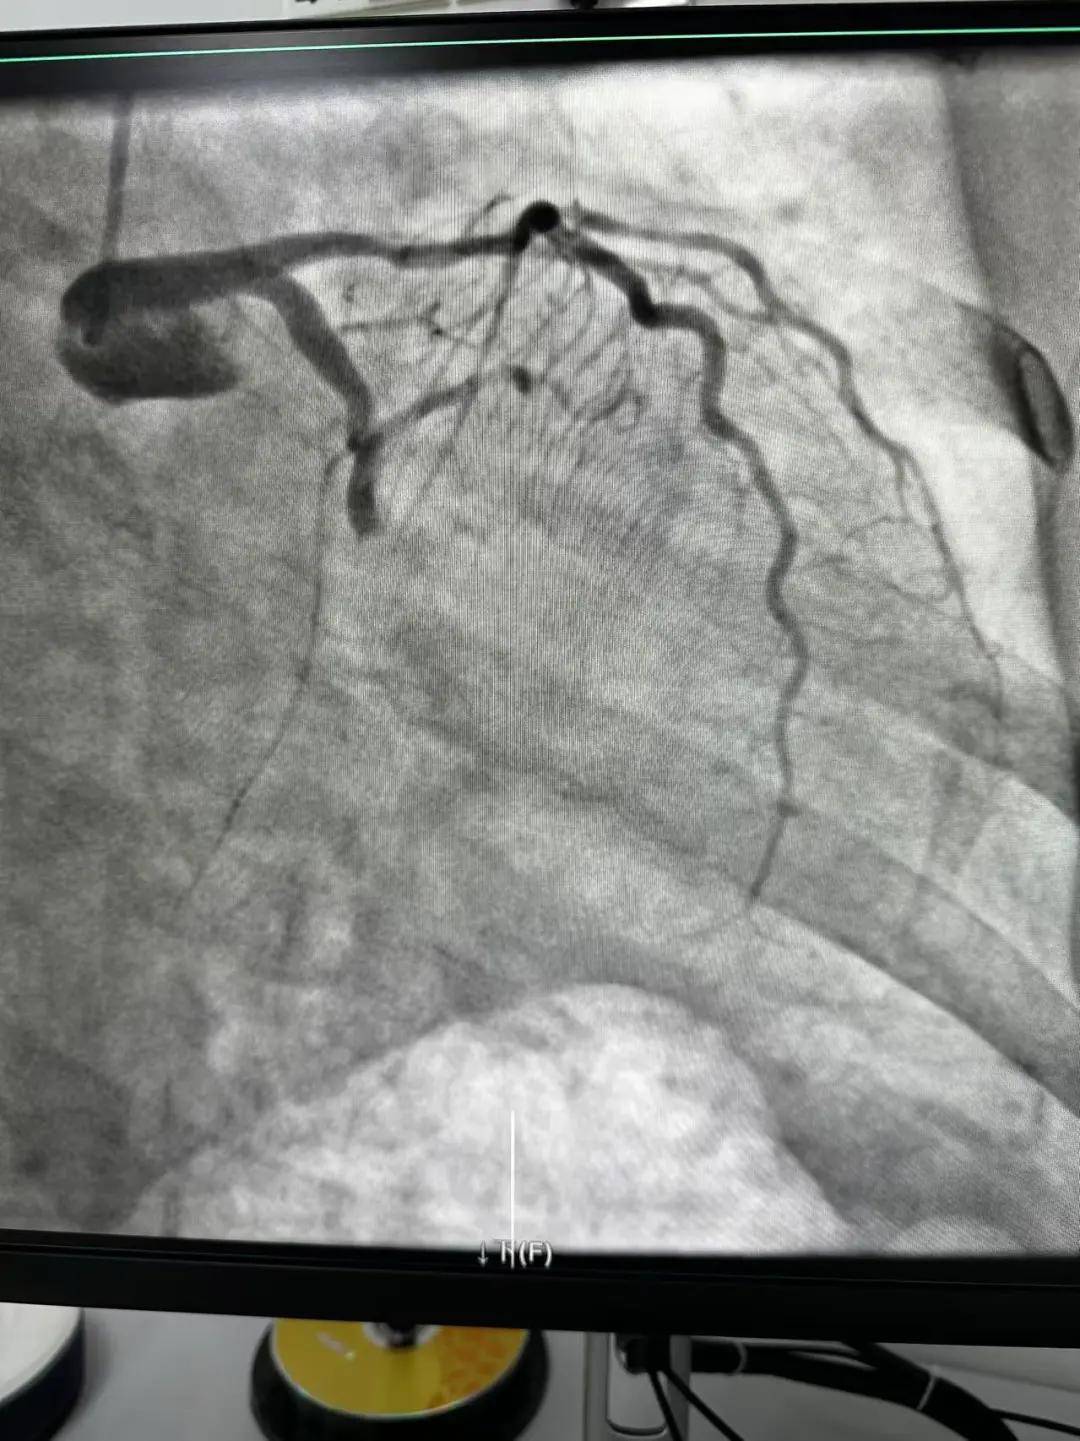

今天最后一臺手術(shù),是一個嚴(yán)重三支病變的病人,患者張大爺,71歲,以“突發(fā)胸悶胸痛3小時”為主訴入院。經(jīng)心電圖檢查后示室上性心動過速,以“冠心病、心絞痛、心律失常”為診斷收住入心內(nèi)科。心內(nèi)科團(tuán)隊通過審慎評估,決定給予患者冠狀動脈造影術(shù)及冠狀動脈內(nèi)支架置入術(shù)。

手術(shù)開臺,在王云峰主任的帶領(lǐng)下,心內(nèi)科團(tuán)隊為張大爺進(jìn)行穿刺。由于病人重聽,在手術(shù)臺上配合度不高,加上病情嚴(yán)重,導(dǎo)致手術(shù)難度加大。手術(shù)正在緊張進(jìn)行中,導(dǎo)管室內(nèi)線電話又急促響起!一位急性心肌梗死患者情況危急,需要緊急進(jìn)行介入治療。

許先生,52歲,大貨司機(jī),在鶴壁至安陽卸貨過程中,突發(fā)胸悶胸痛,伴大汗1.5小時。 患者繞行安陽,于11點38分到達(dá)我院大門,11點41分首份心電圖,提示患者下壁心肌梗死。 起病急,病程短,情況十分危險,如果血管完全堵塞將直接威脅患者生命,亟需疏通堵塞血管進(jìn)行血運(yùn)重建。

時間就是生命,時間就是心肌,救治刻不容緩。王云峰主任立即啟用第二個手術(shù)間進(jìn)行“雙開臺”!將現(xiàn)有人員兵分兩路,兩路人馬各司其職,兩條救心“高速路”為患者火速同時搭建起來。副院長趙清亮也趕到導(dǎo)管室,親自坐鎮(zhèn)指揮。

穿刺、造影、放支架……兩個手術(shù)間各個環(huán)節(jié)緊張卻有序地進(jìn)行著!在心內(nèi)科團(tuán)隊精準(zhǔn)、默契的配合下,兩臺手術(shù)順利完成! 兩名患者的快速、同時、成功救治,得益于殷都區(qū)人民醫(yī)院醫(yī)務(wù)人員快速的應(yīng)急能力、過硬的急救技能,同時更得益于導(dǎo)管室同開臺,保障了救治的迅速有效。